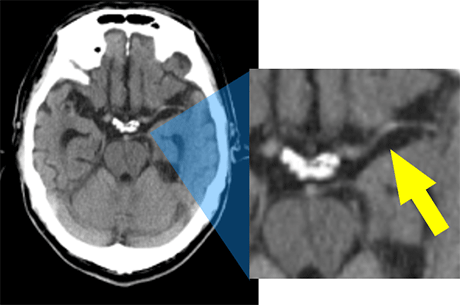

画像再構成においても金属アーチファクト低減機能であるSmart MARを用いることで、いままで目的部位の描出が難しかった、頭蓋内コイル塞栓術後のコイル周囲の観察や歯科治療後の頸部の評価も可能となりました。また脳動脈瘤の手術前のCTA検査に1024Matrixを用いることで、動脈瘤と親動脈の関係、動脈瘤近傍の穿通枝などの小動脈の走行確認など、より詳細な血管描出能も向上しています。

Fig.5 再構成法によるノイズ低減度合いの違い

TFI再構成は、そのノイズ低減度合いを『Low』、『Medium』、『High』の3つのレベルから選択可能です。当院では頭部領域は淡いコントラストにおける境界の視認性を高めるために少しノイズを残した『Low』、その他体幹部などは『Medium』を使用しています。

TrueFidelityイメージング(以下TFI) とはGEヘルスケアのDeep Learning画像再構成技術です。従来機種(Light Speed VCT)の画像再構成法であるフィルタ逆投影(FBP)法は長年CT画像再構成法の主流でしたが、高線量をかけなければ質の高い画像が得られないという課題がありました。TFIでは、高線量FBP画像を教師データとして学習されたモデルを用いることで、従来より低い線量でもアーチファクトの抑制や画像ノイズの大幅な低減を可能としています。